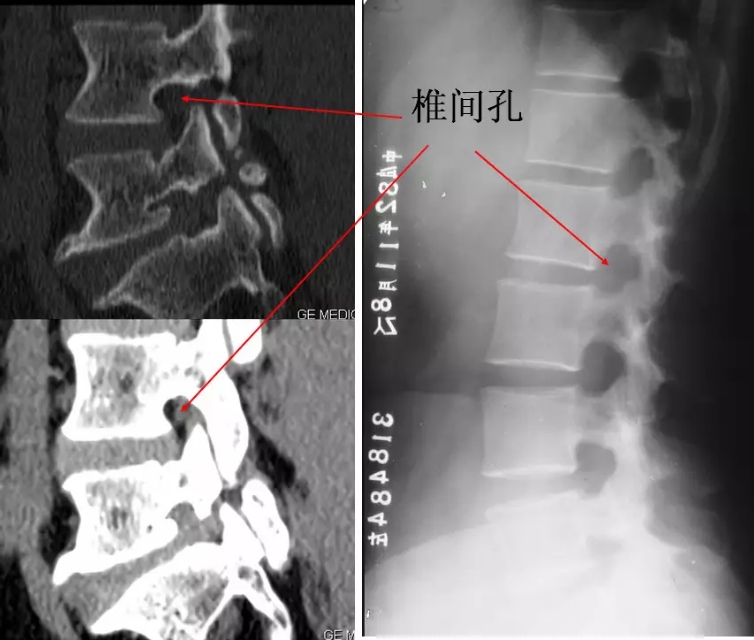

椎间孔:相邻椎弓根、椎体、关节突和椎间盘之间,颈椎在斜位清楚,胸腰椎在侧位清楚。

椎间孔

椎间孔前后径小,钩椎关节增生时易刺激神经根。

椎间隙变窄时,椎间孔上下径亦变小。

椎间孔前为椎体,后为椎小关节,上下为椎弓根,内与侧隐窝相连,有脊神经根通过。

4.滑脱、峡部裂

腰椎前滑脱I度

椎弓峡部裂